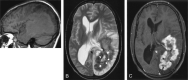

Fig 2.

Brain MR imaging. A, Sagittal T1-weighted image shows the extent of the large mass, which is mostly isointense to gray matter with a mildly hyperintense perimeter. B, Axial T2-weighted image demonstrates the hypointense wall of the mass with surrounding brain edema. Thin, interrupted, low signal intensity zones (arrows) line the margin between the outer wall and central hyperintense necrotic area. C, Axial contrast-enhanced study reveals a thick, irregular enhancing rim. The low signal intensity zones (arrows) do not enhance.